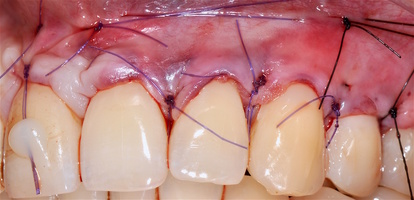

Участки 3.3-3.6 зубов и 4.3-4.6 зубов были проопери- рованы зеркально по методу коронально-ротированно- го лоскута по M. De Sanctis и G. Zucchelli (2000) с одним послабляющим вертикальным разрезом в области 3.3 зуба или 4.3 зуба.

Протокол хирургической операции:

1. Измерены глубины рецессий (ГР), эти замеры отложены от вершин межзубных сосочков в апикальном направлении в сторону зенита рецессии.

2. Дизайн разрезов соответствует методике Zucchelli G. коронально-ротированного смещения (2000).

3. Мобилизация слизисто-надкостничного лоскута, деэпителизация анатомических сосочков, обработка поверхности корней зубов.

4. Фиксация пластического материала ТМО (dura mater) к поверхности корней зубов в области зоны создания необходимого объема прикрепленной десны.

5. Закрытие пластического материала слизисто-надкостничным лоскутом со смещением в корональном направлении, и фиксация слизисто-надкостничного лоскута швами; дополнительная фиксация зоны перемещенных и в будущем созданных мягких тканей десны в зоне рецессии десны для стабилизации результата операции.

6. Обработка поверхностей корней зубов проводилась аналогично (см. выше).